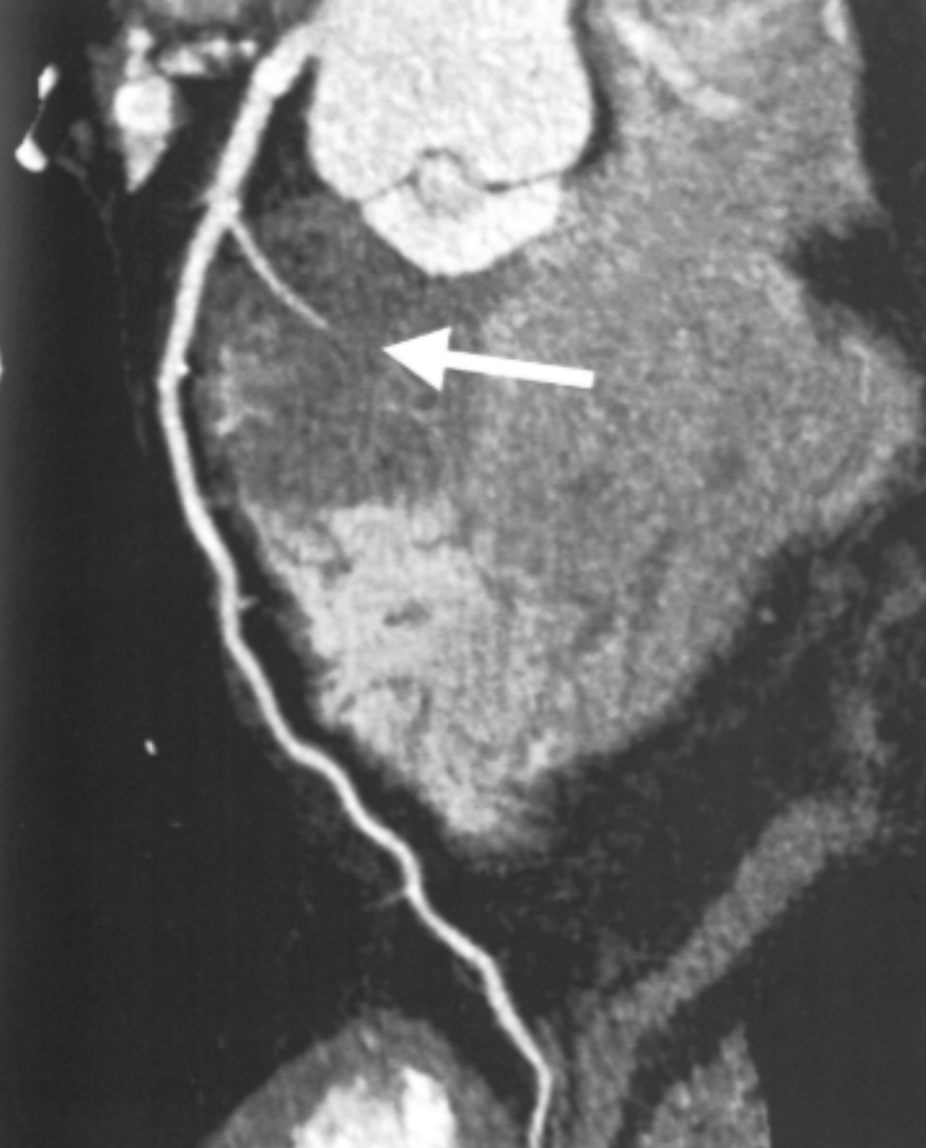

Describe the CT scan protocol/view:

Oblique MIP of the RCA

Describe the RCA findings in this image:

Cardiac Motion Artifact